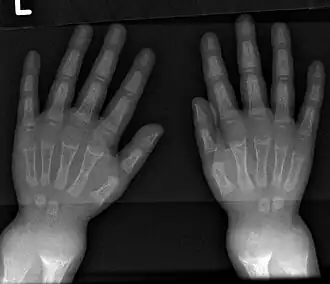

- Radiography typically shows widening of the zones of provisional calcification of the metaphyses secondary to unmineralized osteoid. Cupping, fraying, and splaying of metaphyses typically appear with growth and continued weight bearing.[47] These changes are seen predominantly at sites of rapid growth, including the proximal humerus, distal radius, distal femur, and both the proximal and the distal tibia. Therefore, a skeletal survey for rickets can be accomplished with anteroposterior radiographs of the knees, wrists, and ankles.[47]